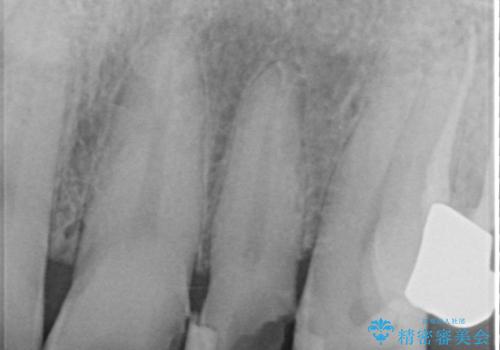

また、右上側切歯は根管治療が必要な状態でした。

右上側切歯に対して根管治療を行い、その後右上側切歯から左上犬歯まで計5本をオールセラミッククラウンで補綴する治療計画をご提案しました。